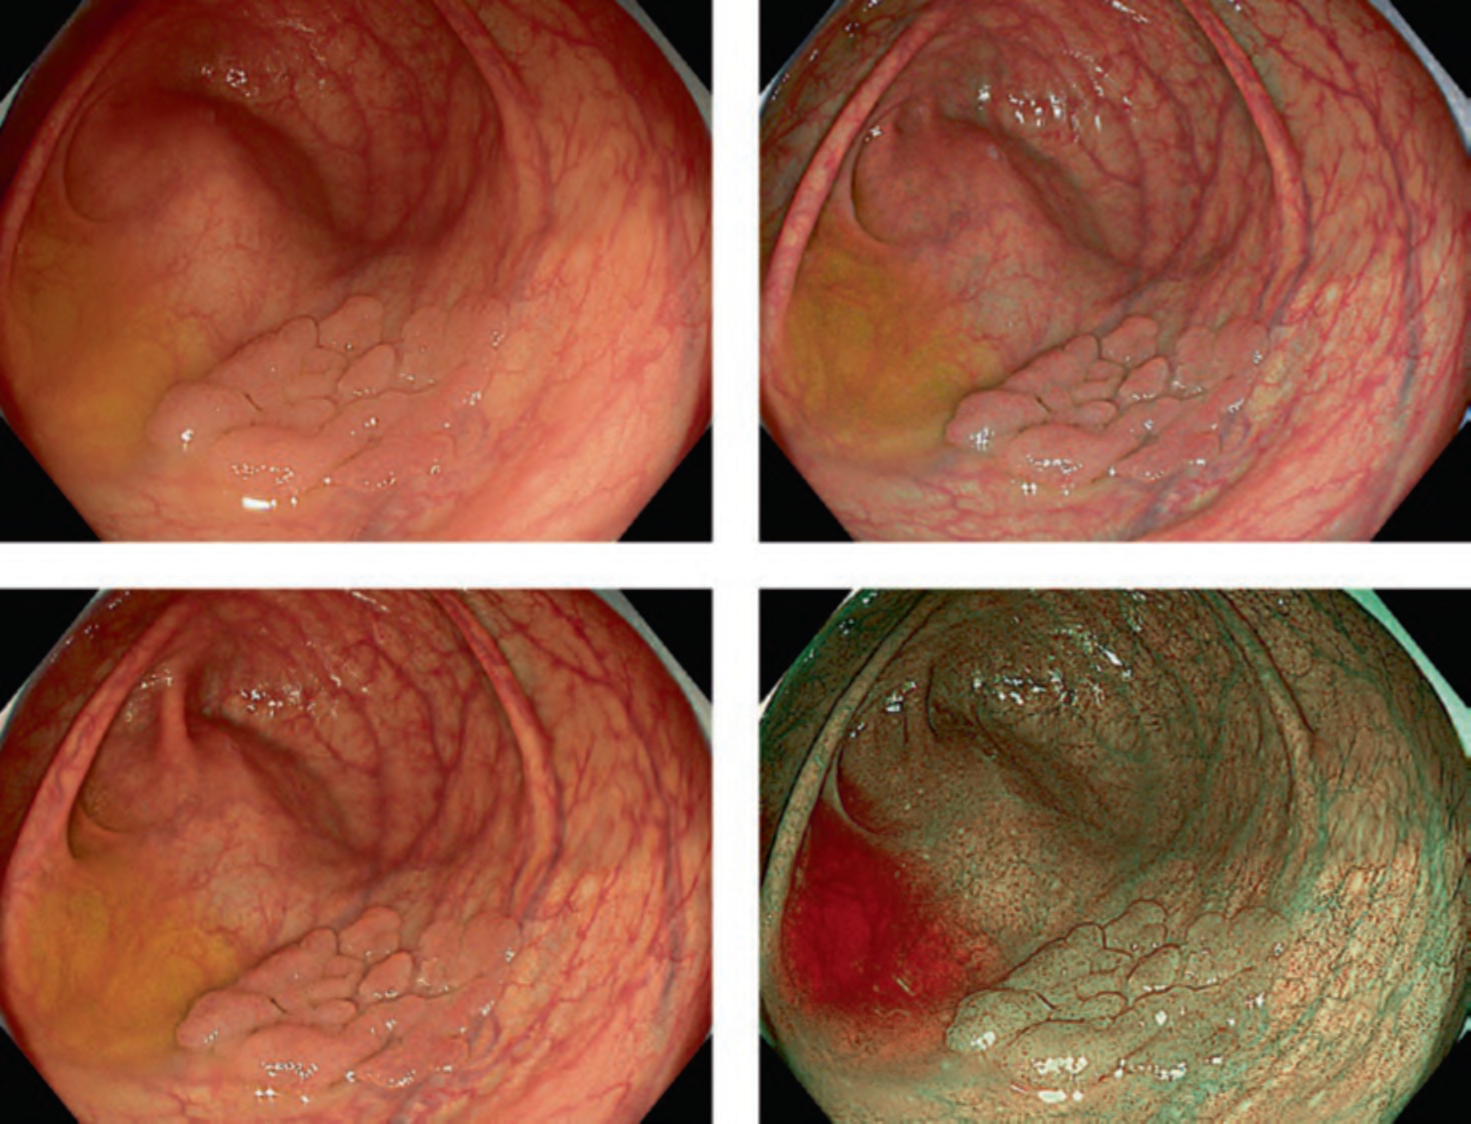

The VS classification system developed by the author (Kenshi Yao) [1] is the most widely accepted diagnostic system for magnifying narrowband imaging (M-NBI) of the stomach [2]. The VS classification system employs anatomical terms as endoscopic markers for analysis. Anatomical components visualized using M-NBI were divided into microvascular (MV) and microsurface (MS) patterns. As shown in . Fig. 1a–c, the subepithelial capillary and collecting venule were visualized for MV pattern, while the marginal crypt epithelium (MCE), crypt opening (CO), and intervening part (IP) between the crypts were identified for the MS pattern. In addition, in terms of the pathological status, the light blue crest [3] and white opaque substance [4] can be markers for microsurface patterns.

According to the morphology of the anatomical components, the MV and MS patterns were classified as regular, irregular, or absent (. Fig. 2). In principle, the MV and MS patterns must be determined separately.

DL is defined as the border between the lesion and non-lesion areas, discernible through an abrupt change in MV and/or MS patterns (. Fig. 2).